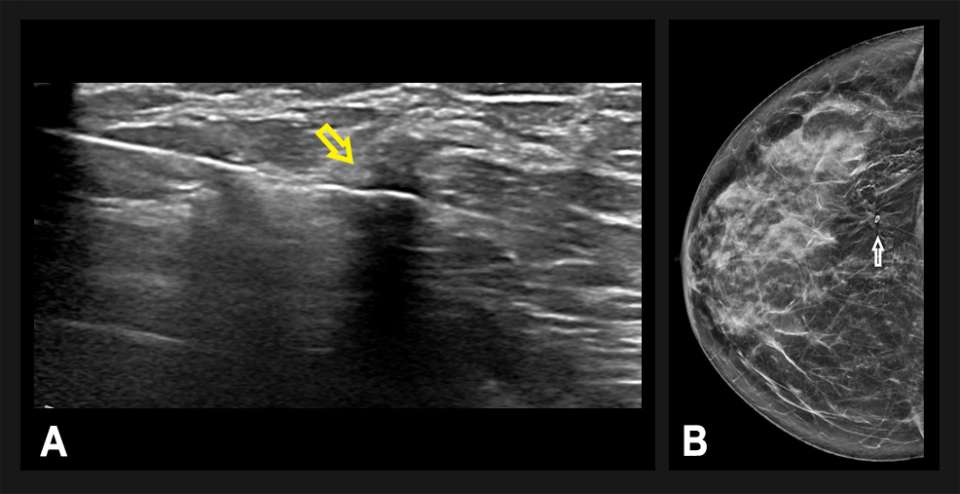

A technically-successful ultrasound-guided biopsy was performed, with 6 core samples obtained (Figure 3). A post-biopsy mammogram confirmed accurate positioning of the biopsy microclip at the site of architectural distortion. Pathology revealed invasive ductal carcinoma, grade 1 estrogen receptor negative, progesterone receptor negative, and HER2 positive. The patient underwent a right breast lumpectomy and sentinel lymph node biopsy, followed by adjuvant radiation.